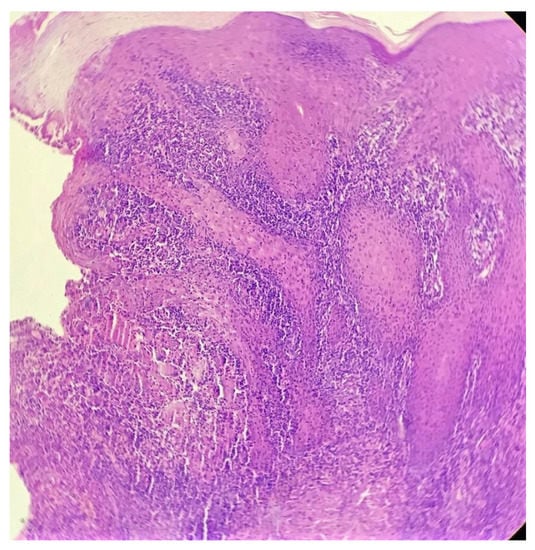

Biopsy showed a dense lichenoid and loose tuberculoid granulomatous infiltrate comprising of epithelioid cells, histiocytes and occasional Langhan’s giant cells, surrounded by lymphocytes and few plasma cells. The granuloma was seen abutting the overlying epidermis, which showed psoriasiform hyperplasia with mild to moderate spongiosis. A compact tuberculoid granuloma was also seen in the deep reticular dermis. Fibroplasia was also seen in the dermis (Figure 2, Figure 3, Figure 4 and Figure 5). The PAS-stained sections were negative for fungal organisms. Zeil–Neelsen stained sections did not reveal any acid-fast bacillus. Based on these features, a diagnosis of lupus vulgaris was favoured and further confirmation by culture study and PCR was advised.

Figure 2. Lichenoid granulomatous dermatitis pattern with psoriasiform epidermal hyperplasia (H&E × 40).